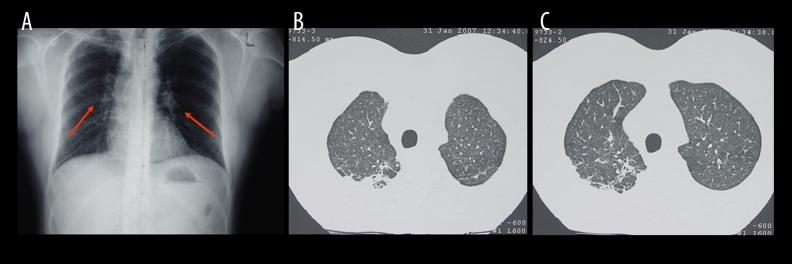

BACKGROUND Ocular tuberculosis (TB) is a clinical entity that presents with a wide range of clinical manifestations. It is regarded as an extremely challenging condition from the point of view of diagnostic approach and calls for early diagnosis and prompt treatment, as it can potentially lead to blindness. CASE REPORT This is a case report of a 32-year-old male from southern India who has been living and working in Greece over the last 10 years and presented with 2-week history of pain and progressive visual impairment of his left eye. He underwent a thorough clinical ophthalmological examination and imaging of the fundus, and the findings were consistent with uveitis. However, the manifestations of the inflammation were complicated as they included features that could be attributed mainly to Vogt-Koyanagi-Harada (VKH) disease and tuberculous serpiginous-like uveitis. Therefore, a systemic evaluation, together with specific laboratory and paraclinical investigations, were carried out to define the etiology of the inflammation and develop an optimal therapeutic plan. Taking into account specific findings from the chest imaging, a positive purified protein derivative (PPD) skin test, and sputum cultures positive for Mycobacterium tuberculosis (MTB), we set a diagnosis of posterior sclero-uveitis and started our patient on anti-tuberculous treatment. CONCLUSIONS This case reveals an atypical manifestation of tuberculous sclero-uveitis imitating Vogt-Koyanagi-Harada disease together with a few characteristics of serpiginous-like tuberculous uveitis, emphasizing the fact that tuberculosis should always be included in the differential diagnosis of uveitis when there is no obvious underlying disease.